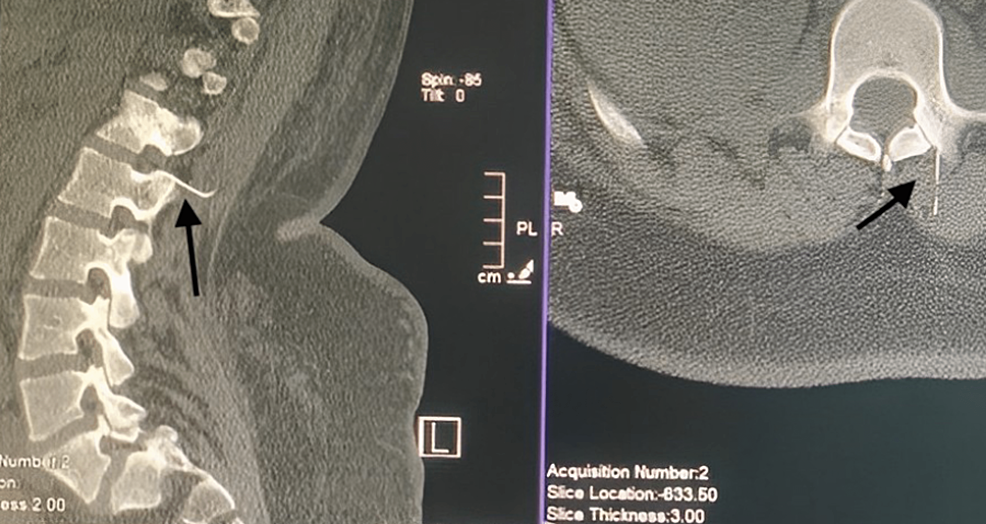

Thoracic Spine Image